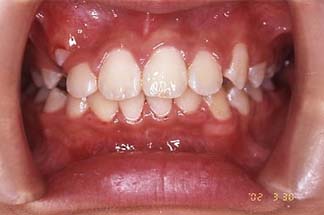

過蓋咬合(第一期のみ)

治療前

| 主訴 | 下の前歯の乱杭歯 |

|---|---|

| 診断名 | 下顎前歯の叢生を伴う過蓋咬合 |

| 初診時年齢 | 8歳3か月 |

| 主な治療装置 | 上下顎歯列弓拡大装置、前歯部ブラケット装置 |

| 抜歯部位 | 非抜歯 |

| 治療期間 | 1年2か月 |

| 治療費 | 矯正治療基本料 30万円 / 調整料3000円~5000円×15回 |

| リスク・副作用 | 矯正中は、口腔を清潔に保たないと、虫歯、歯肉炎、歯周病になるリスクがあります。ブラケット装置の使用には、口腔内の刷掃や治療協力が必要です。治療後の保定を怠ると、このような症例では、後戻りが容易に起こるので長期管理が必要です。 |